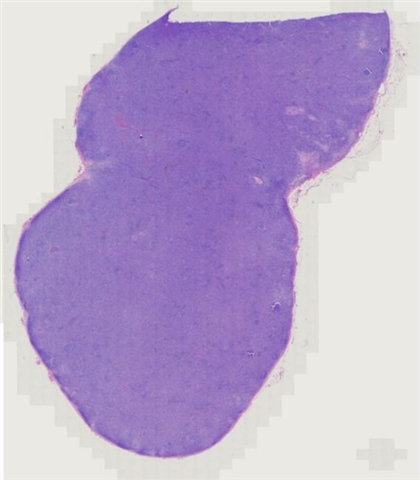

案例5 (6864)

性别:       年龄:62

患者详情: 发现双侧腹股沟肿物1月余。 查体: 双侧腹股沟可扪及多发肿大皮下肿物,大小约2*2cm,质中,边界尚清楚,活动度可,伴压痛,表面皮肤未见红肿破溃。 B超: 双侧腹股沟淋巴结肿大。 病理检查:腹股沟淋巴结穿刺活检提示淋巴组织增生。随行左侧腹股沟淋巴结切除术。

大体所见: 结节状肿物1枚,大小3×2×1.5cm,表面附有包膜,切面灰白灰红色,实性,质中。

医院: 上海长海医院